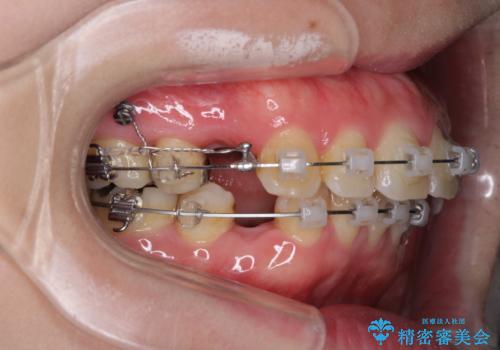

- クリアブラケット

- 2年2ヶ月

- 口が閉じずらく、口元が突出している状態でした。

上下左右の歯を1本ずつ、合計4本抜歯して、ワイヤーにて矯正することとなりました。

もともと下の前歯の永久歯が1本欠損しており、抜歯部位の選択を考慮しなければならない症例でした。シミュレーションを事前に行い、下顎の抜歯部位を決定しました。